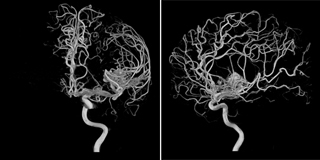

MRI(磁気共鳴イメージング)検査は、放射線科の他の検査で紹介しているX線等を用いた検査と異なり、強い磁石と電波を用いて身体の内部の状態を検査する方法です。内容によっては注射をすることもありますが、身体を傷つけることなくじっとしているだけで、下の図のように血管の画像やいろいろな角度から、いろいろなコントラストで身体の断面の画像を撮像することができます。

当院では2台のMRI装置が稼働しています。1台はより強い3T(テスラ)の磁力でより精密に画像化することが可能な最新の技術を搭載したシーメンス社製MRI装置で、放射線科内にて稼働しています。もう1台は1.5Tの磁石の強度をもち、救急にもいち早く対応できるよう診療支援棟にて稼働し、身体のあらゆる部位を画像化でき、新しい技術も盛り込んだフィリップス社製MRI装置です。ともに、従来よりも検査を受ける方に優しいトンネル部分が大きくなった装置で、閉所に弱い方でも負担の少ない配慮された装置です。